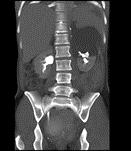

问题 男,28岁,交通事故受伤,查体:有休克症状,请结合CT图像,选择最可能诊断 ( )

选项 A、脾破裂 B、腹膜后出血 C、左肾裂伤并大血肿形成 D、左肾包膜下出血 E、左肾挫伤

答案 C